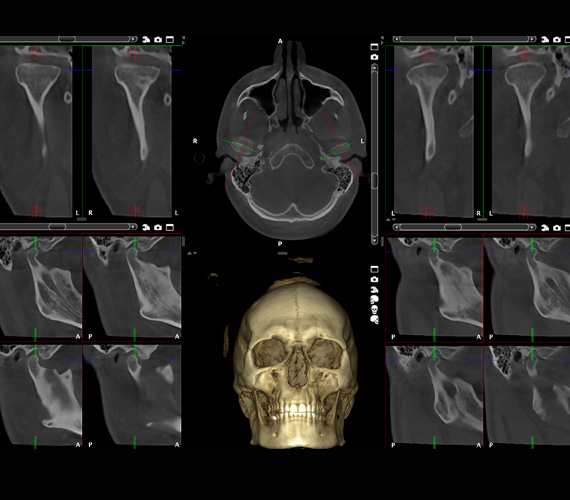

Temporomandibular joint (TMJ) pain affects a significant part of the population. Planmeca Romexis provides views especially designed for examining and analysing TMJ concerns. Both of a patient’s joints can be evaluated at the same time within the software, with precise measurements also created.